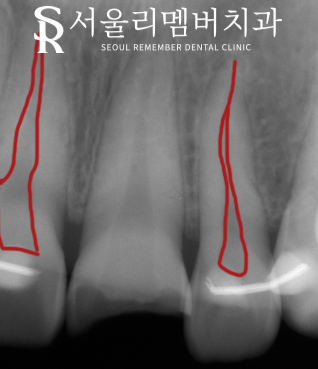

방사선 사진을 통해 머리 부분만이 아니라 뿌리 부분에도 파절이 있는지 확인을 해야 됩니다.

방사선 사진을 찍어봤을 때 가운데 검은색 빈 공간(신경관)처럼 보이는 곳에 이미 침범한 것을 것을 볼 수 있었습니다.